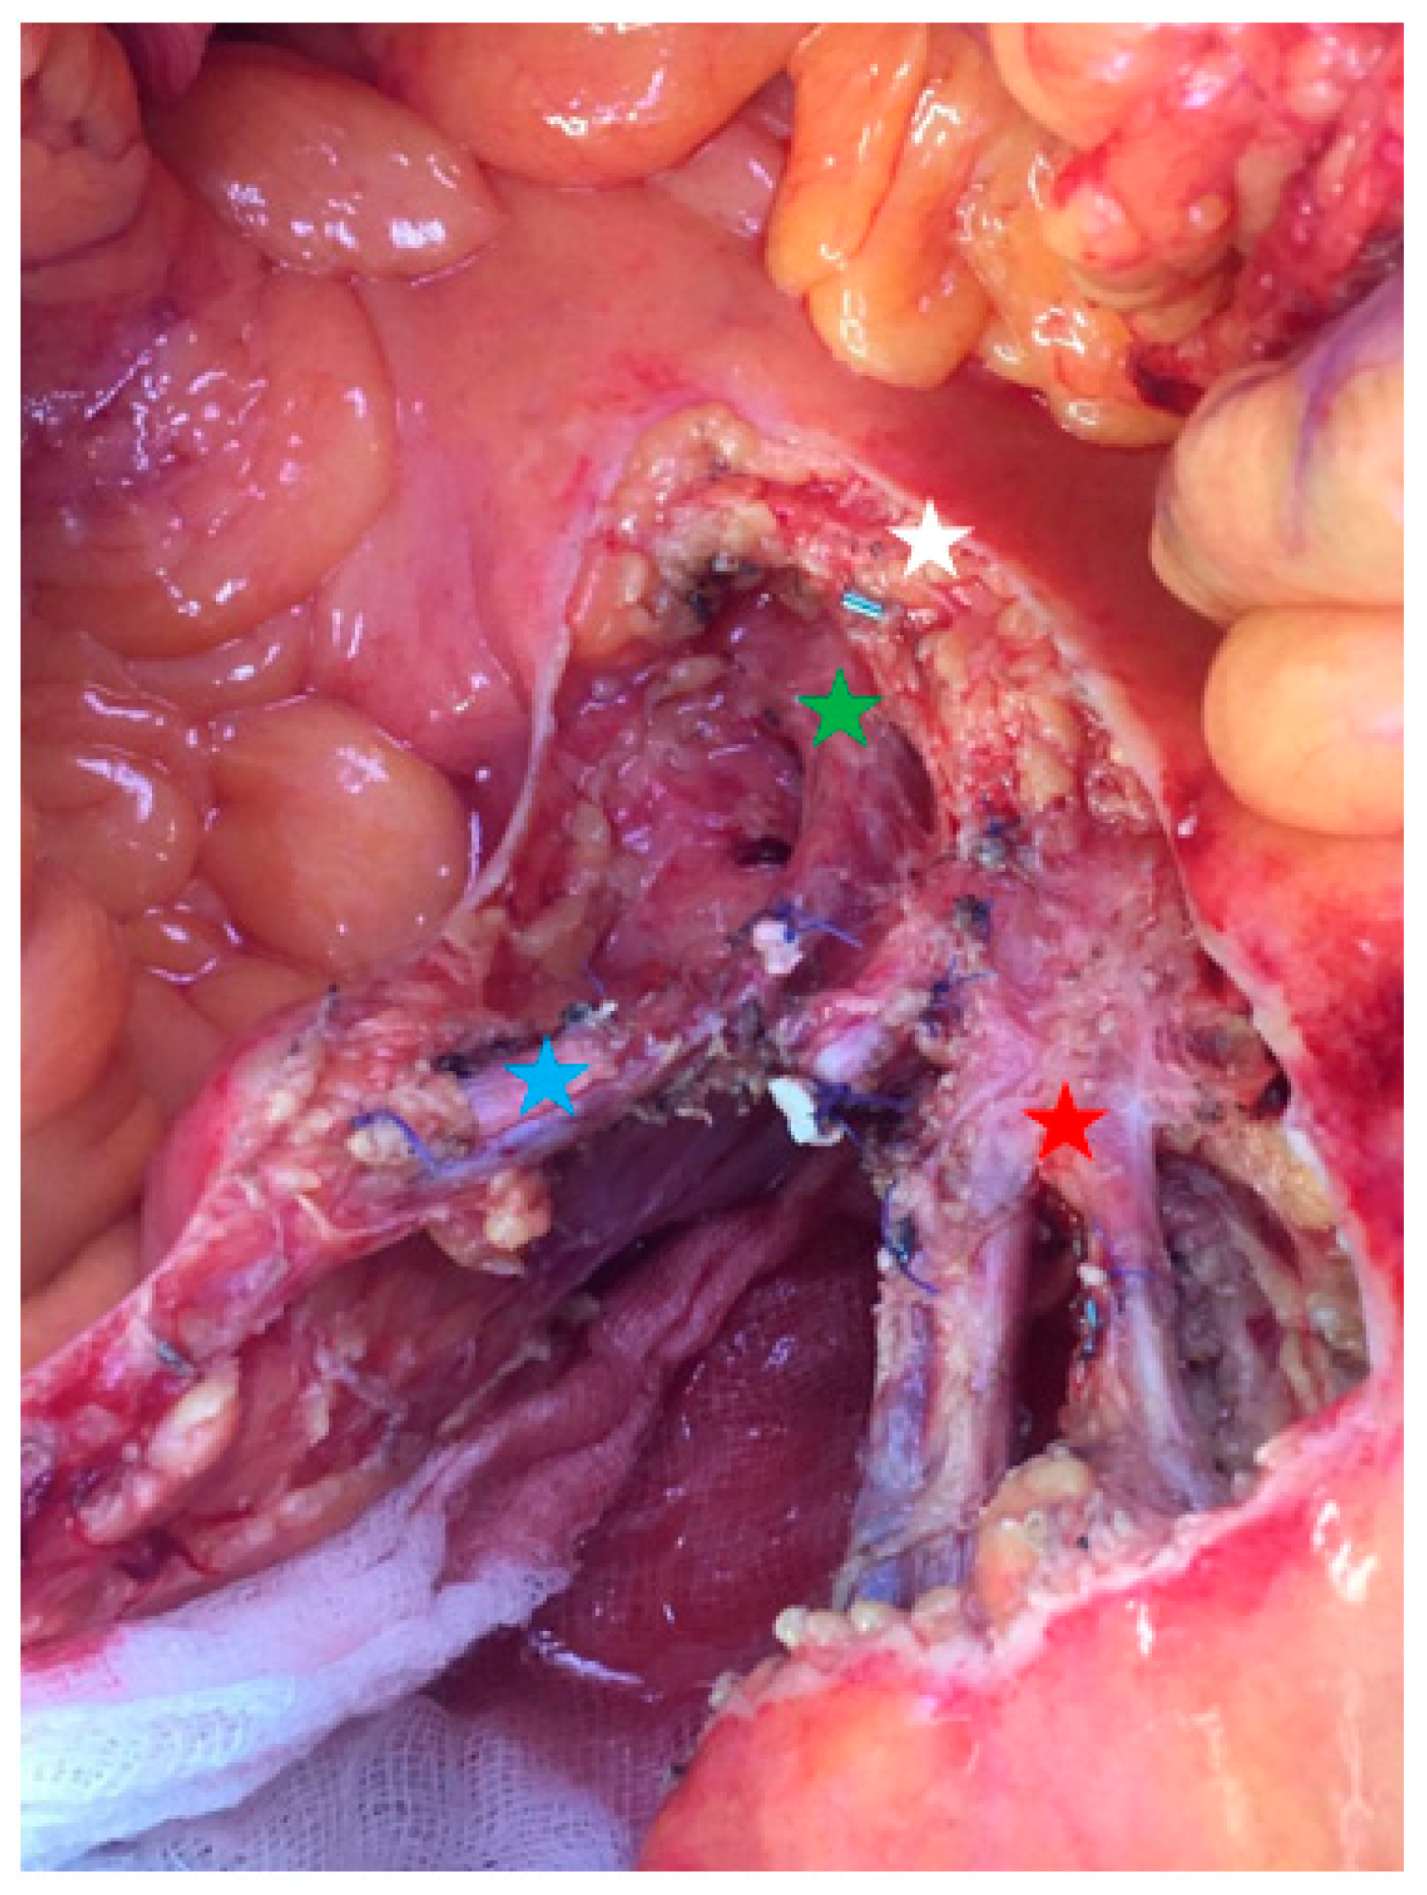

The resection starts with dissection of the mesenteric vessels to determine whether the mesenteric nodal block is resectable. Then, the retroperitoneum is opened, followed by a Kocher maneuver to expose the proximal part of the superior mesenteric artery. This strategy allows progressive ligation of vascular branches without any threat to uninvaded jejunal arteries. Lymphadenectomy is performed above the right colic vessels if the nodal mass is located on the right part of the mesenteric axis. If the nodal mass only implies the left side of mesenteric artery, the right superior colic artery can be preserved if the mass is located below its origin. Right hemicolectomy is not mandatory in all patients. Next, the dissection is pursued on the left border of the superior mesenteric vessels. A minimum of three jejunal branches have to be free to avoid the risk of short bowel length [6,13]. Then, the length of the devascularized small bowel determines the resection’s limit (Figure 4). Due to the collateral circulation, the ischemic small bowel segment is usually shorter than expected. Extensive lymphadenectomy can be performed from the small bowel section to the superior mesenteric dissection, with special attention paid to any jejunal pedicle that could be preserved (Figure 5). The length of the remaining small bowel should be measured and recorded. Techniques of reconstruction do not differ from any digestive surgery anastomosis and should be performed according to the experience of the operator.

Figure 5.

Operative view focusing on the proximal nodal resection (group 3). Red star: proximal jejunal arteries and veins; blue star: superior right colic artery and vein; green star: superior mesenteric vein; white star: pancreas.